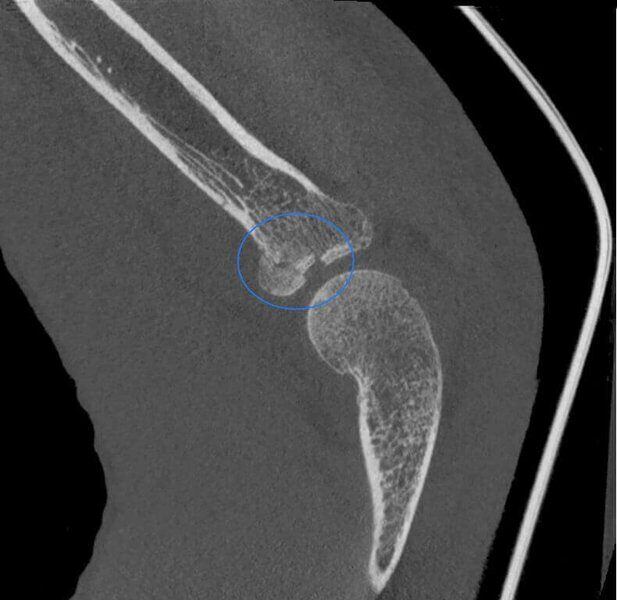

Fractura de la cabeza del radio en paciente con yeso.